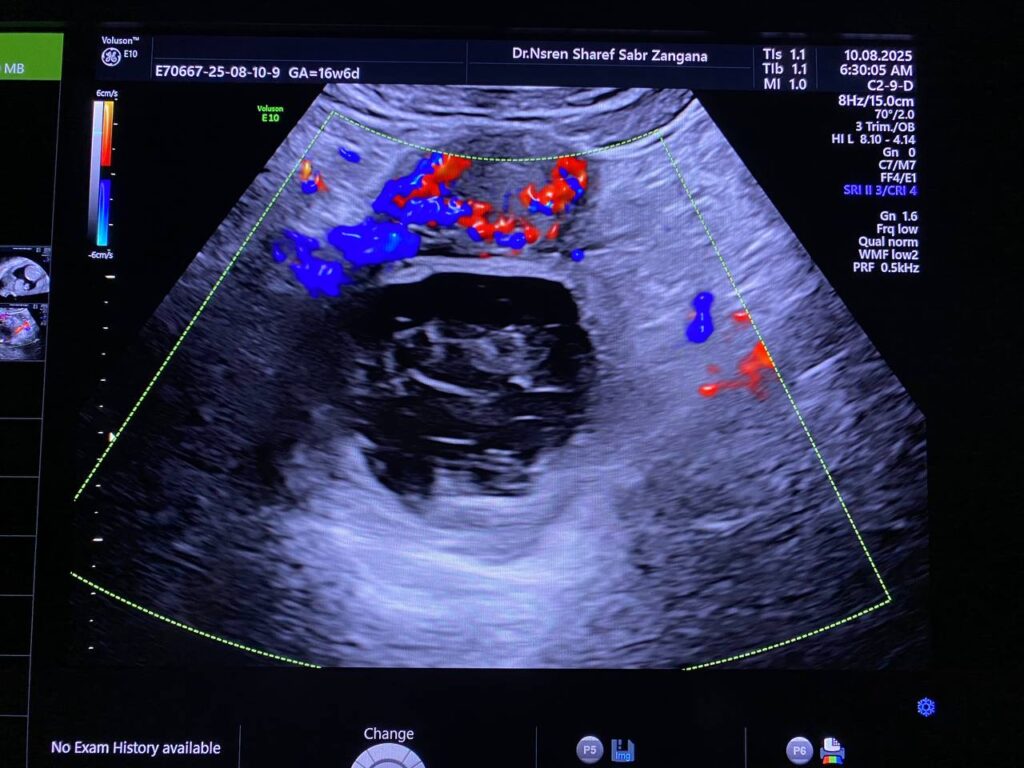

Right ovarian heterogeneous circumscribed avascular cystic mass its size 55x55mm, mostly hemorrhagic , with whirlpool sign , picture mostly of Twisted right hemorrhagic ovarian cystic , Cystic TORSION , please for further study ??

· No free pelvic fluid seen